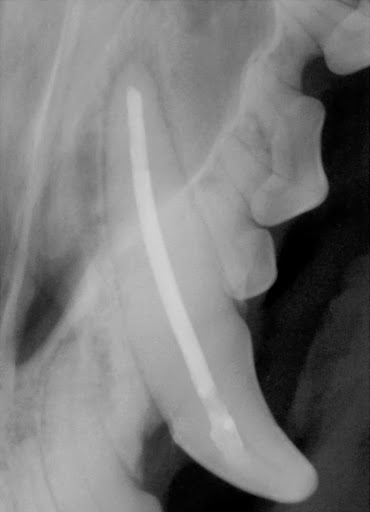

Dr. Beebe was a miracle worker yesterday afternoon. Our 4 month old puppy was attacked by another dog, which resulted in two breaks in the left lower jaw- completely detaching the bone from the mandible. Due to his age and puppy teeth, there were extremely limited options on how to operate and attempt to fix the break, no veterinarian dentist in the Denver area felt confident taking the case. But Dr. Beebe helped us out immensely by taking our little guy in on the same day and doing his surgery into the evening hours. He thought outside the box and creatively and miraculously combined several different methods to piece his jaw and tissue back together. He and his helpful staff talked us through the whole event, didnt mind when we called throughout the long surgery to check in, and in a deeply traumatic incident made us feel so much better. In the midst of a terrible day, we were lucky to be referred to Apex Dog and Cat Dentistry. We are so thankful.